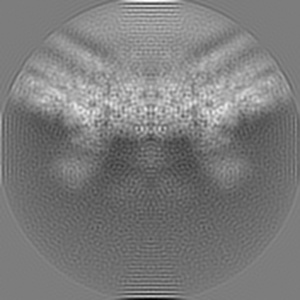

Cryo-EM structure of dengue virus serotype 3 strain 863DK in complex with human antibody DENV-115 Fab at 4 deg C (subparticle LLR-LRR)

Single-particle4.1 Å

Sample: Dengue virus serotype 3 strain 863DK in complex with human antibody DENV-115 Fab at 4 deg C